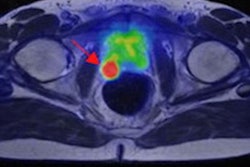

Prostate cancer staging is a rapidly evolving area, and PET/MRI is generating particular excitement among researchers.

The preliminary results of an intriguing new study conducted at the prestigious IRCCS Ospedale San Raffaele in Milan have been unveiled recently. Given the complex nature of research like this, it's understandable that the sample size was relatively small, but the findings still deserve a close look in an article posted today.